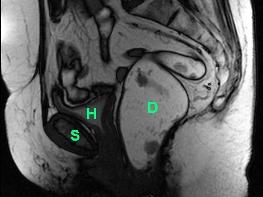

Magnetresonanz-Defäkographie

Eine andere wichtige Untersuchung stellt die Magnetresonanz-Defäkographie dar. Hierbei handelt es sich um eine funktionale Untersuchung, durch die die Bewegung des Beckenbodens während des Stuhlgangs (Defäkation) aufgezeichnet und als Filmsequenz dargestellt werden kann. Mit Hilfe dieser Untersuchung, bei der keine Belastung durch Röntgenstrahlen auftritt, können Veränderungen des Beckenbodens entdeckt werden, welche nur während des Stuhlgangs auftreten.

Die Abbildungen unten zeigen eine dynamische Untersuchung des Beckenbodens mittels Magnetresonanz-Defäkographie: Ruheposition (Abb. links) und Defäkation (Abb. rechts). Der Enddarm zeigt nach Kontrastmitteleinlauf ein helles Signal (D). Am Ende der Defäkation bildet sich eine grosse Rectocele aus (Pfeil), welche sich unter die Harnblase (H) und bis unter die Symphyse (S) schiebt. Der Enddarm kann sich aus diesem Grund nicht vollständig entleeren. Zusätzlich kommt es zu einem Tiefertreten der Harnblase (H, Abb. rechts) im Sinne einer Beckenbodenschwäche.